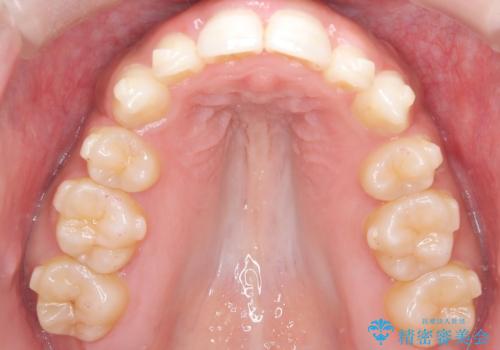

- 「前歯が出ていて並びも悪いのが気になる」との主訴で来院されました。診察の結果、上顎前歯の前突と中等度の叢生(ガタつき)が認められ、歯がきれいに並ぶスペースが不足していました。横顔のバランスと歯並びの両方を整えるため、上顎の左右の第一小臼歯2本を抜歯し、前歯を内側に下げながら歯列全体を整える治療計画を立てました。

患者さんのご希望もあり、取り外しが可能で目立ちにくいインビザライン(マウスピース矯正)を選択。抜歯スペースを活用しながら、叢生と前突感の改善を同時に目指しました。

治療はインビザラインによって進め、抜歯スペースを使って前歯を内側に引き込みながら、歯のガタつきも順に整えていきました。初期の段階で前歯の見た目が大きく変わり、患者さんにも「印象が柔らかくなった」と非常に喜んでいただけました。

しかし、途中で来院が途絶えてしまい、インビザラインのアカウント(治療管理期間)が終了。再発注やリカバリーが難しくなったため、治療再開のためにワイヤー矯正の提案を行いましたが、患者さんのご希望により再治療は見送られることとなりました。